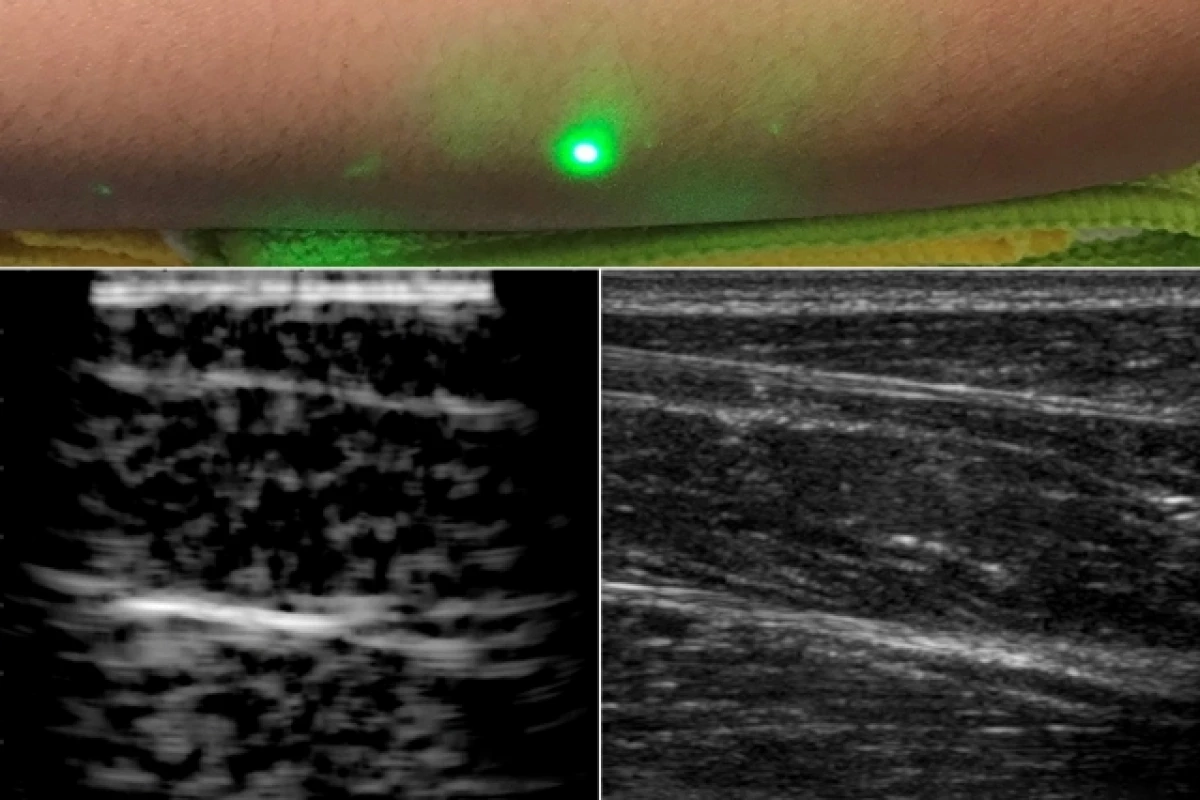

3d ultrasound 4d ultrasound and hd ultrasound 3d ultrasound is a single detailed image of your babys face. Please note that our 3d ultrasounds and 4d ultrasounds can only be performed on pregnant women who are under the care of a physician.